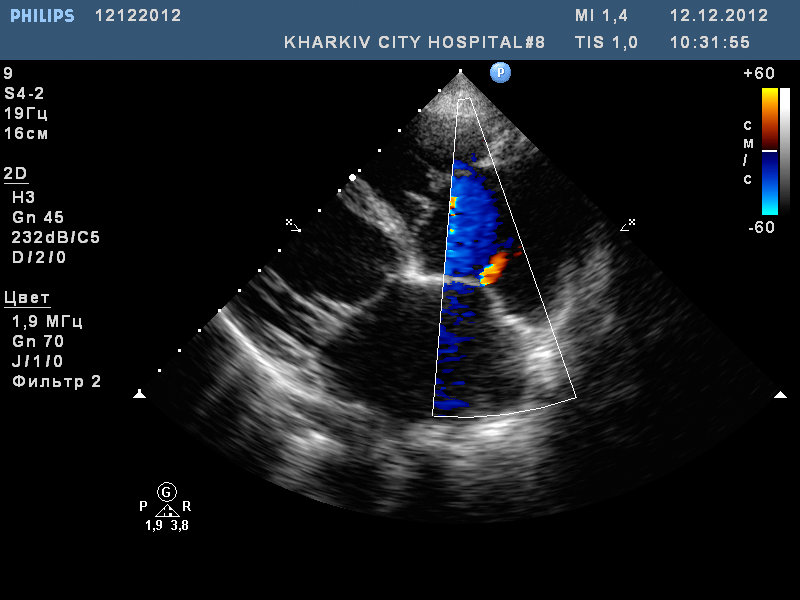

Открытое овальное окно. Пациент госпитализирован с пароксизмом мерцательной аритмии.

Кстати у этого пациента не было год назад сброса крови. Произошла обьемная перегрузка предсердий в течении времени, дилатировались предсердия ( в частности левое) и появилась такая картина.

на фоне 8 дней терапии и с восстановленым ритмом у данного пациента не лоцируется сброс.

ООО теперь ЗОО